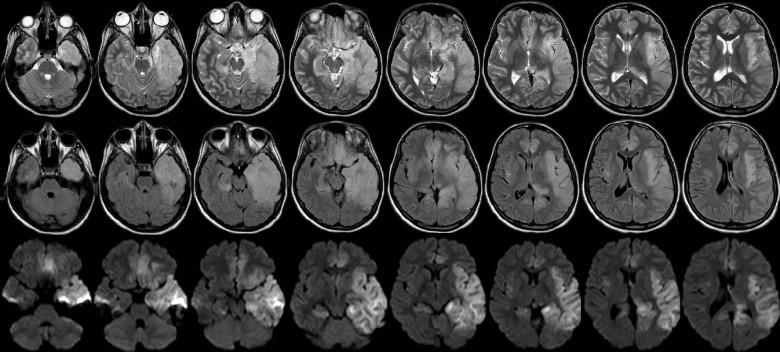

Herpes simplex virus (HSV) encephalitis, predominantly caused by HSV-1, presents with significant morbidity and mortality challenges. This research investigates the particular role of adjunctive corticosteroid therapy in fulminant HSV encephalitis through in-depth analyses of two contrasting cases. Corticosteroids show potential benefits to improve an exaggerated immune response and limit viral dissemination within the brain. Daily assessments and frequent neuroimaging, particularly using magnetic resonance imaging, aid in the management of fulminant cases. Although existing evidence relies on limited case series and retrospective comparisons, the results of the present study emphasize the necessity for large-scale controlled trials to establish definitive guidelines. The discretion of the treating neurologist governs the decision to implement corticosteroids, emphasizing the imperative need for continued research and evidence-based strategies for this challenging neurological condition.

单纯疱疹病毒(HSV)脑炎主要由HSV-1引起,带来了显著的发病率和死亡率挑战。本研究通过对两个对比病例的深入分析,探讨辅助性皮质类固醇疗法在暴发性HSV脑炎中的特殊作用。皮质类固醇显示出潜在益处,可改善过度的免疫反应并限制病毒在脑内传播。每日评估和频繁的神经影像学检查,尤其是使用磁共振成像,有助于暴发性病例的管理。尽管现有证据依赖于有限的病例系列和回顾性比较,但本研究结果强调了进行大规模对照试验以制定明确指南的必要性。治疗神经科医生的判断决定了是否使用皮质类固醇,这凸显了针对这种具有挑战性的神经系统疾病持续开展研究和采用循证策略的迫切需求。